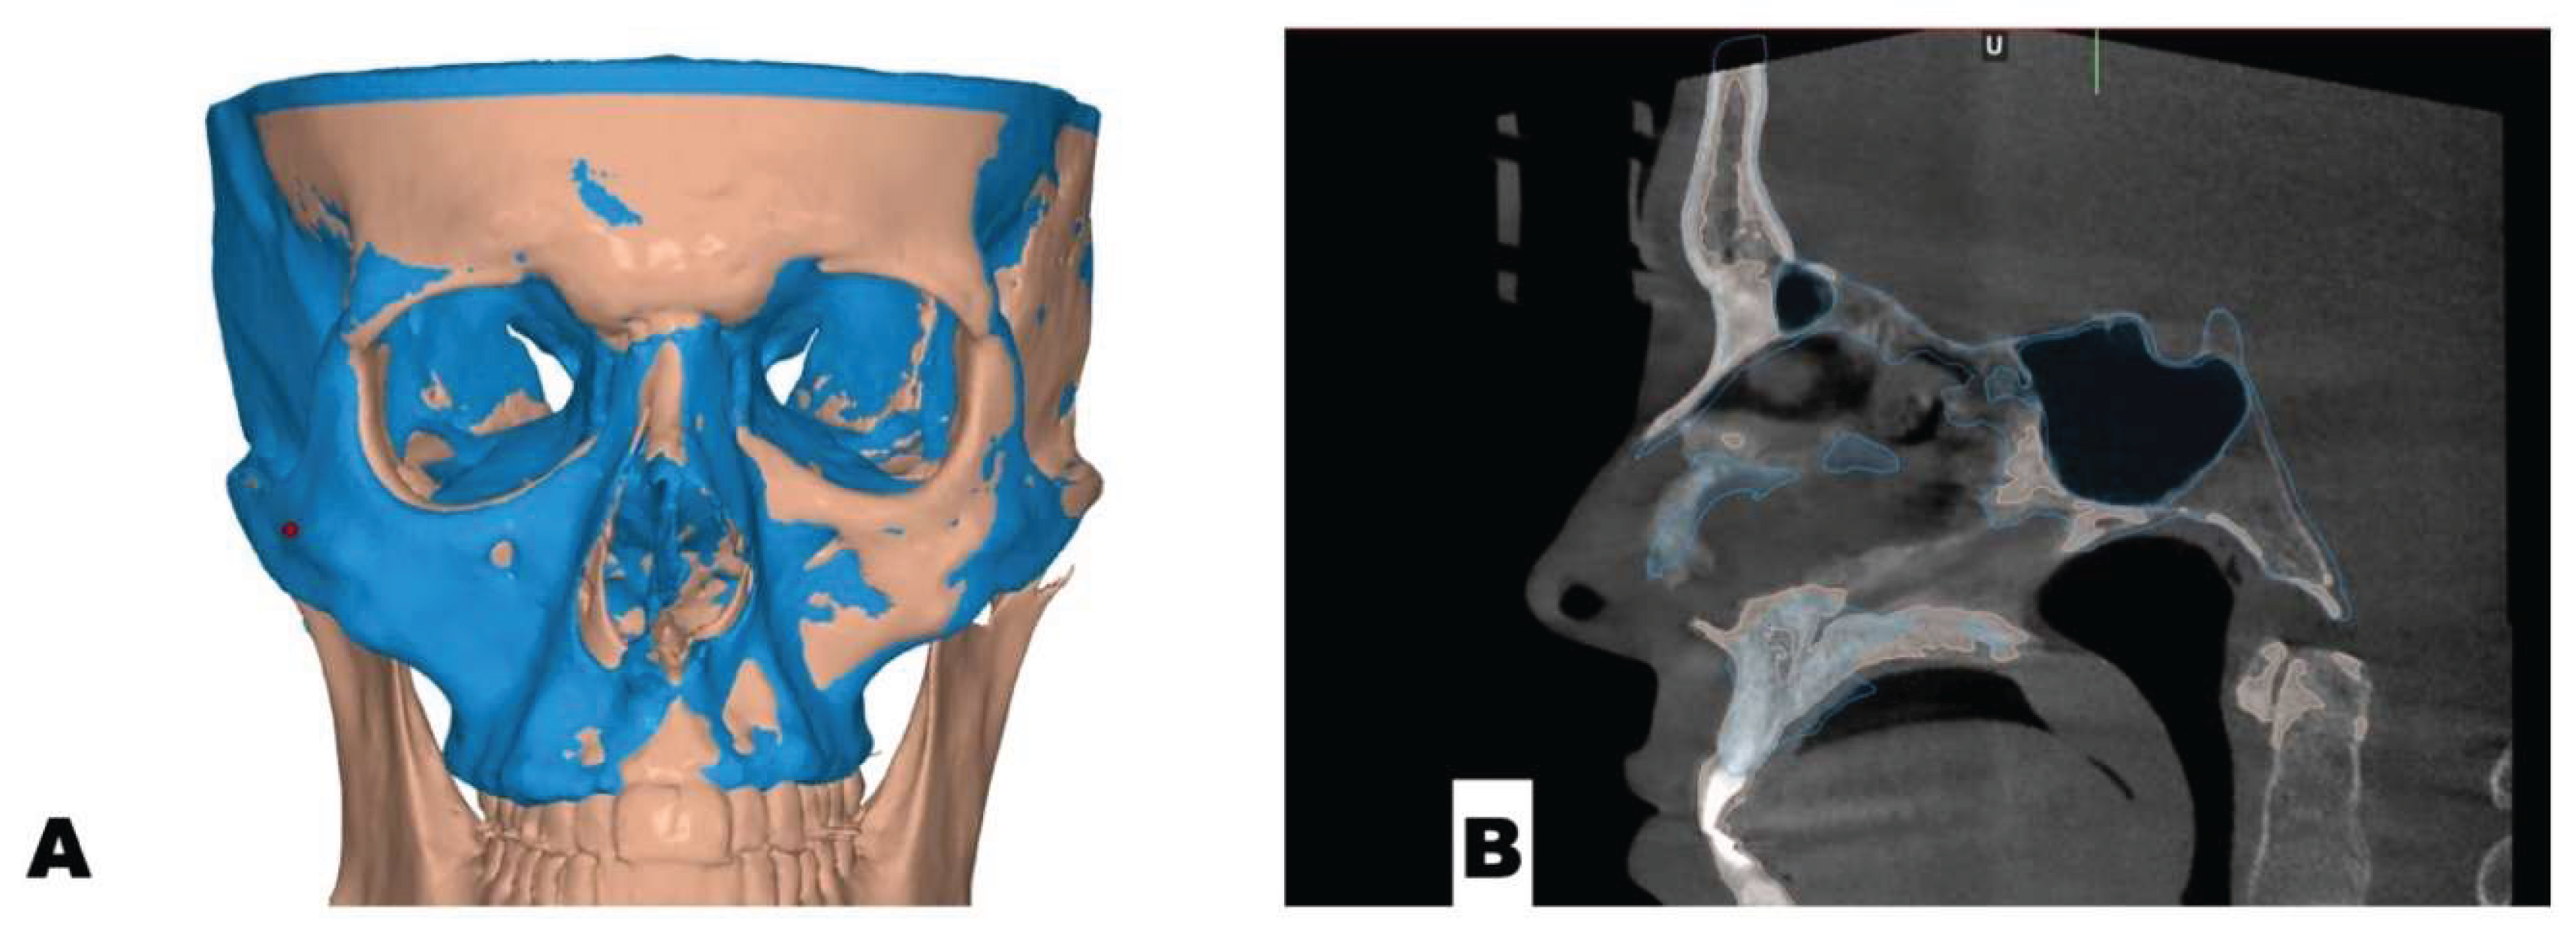

Background: While mini-screw-assisted rapid palatal expansion (MARPE) is effective for correcting maxillary transverse deficiency in adults, perimaxillary suture disarticulation—particularly at the pterygomaxillary junction—can be inconsistent. This study evaluates skeletal and dentoalveolar outcomes of a novel 3D-guided midpalatal piezocorticotomy-assisted MARPE protocol, focusing on expansion symmetry and pre-existing asymmetries. Methods: Three adult patients were retrospectively analyzed after treatment with 3D-guided midpalatal piezocorticotomy-assisted MARPE expansion and one with non-guided midpapalatal piezocorticotomy and MARPE expansion. Surgical guides were digitally designed using CBCT data to align with the nasal septum orientation in multiple planes. Perimaxillary suture disarticulation was measured pre- and post-expansion, and dentoalveolar changes were evaluated. Post-expansion asymmetries were addressed using directly printed aligners. Results: Complete midpalatal suture separation (mean 8.48 mm), involving both anterior and posterior nasal spine regions, was achieved in one patient. Bilateral pterygomaxillary disarticulation averaged 1.06–1.23 mm, resulting in forward–outward rotation of the nasomaxillary complex. Additional separation occurred at the frontonasal (2.03 mm) and vomeromaxillary (1–2 mm) sutures, with no significant changes in orbital or peri-orbital sutures. One patient presented with pre-existing dentoalveolar asymmetry, which intensified the perceived post-expansion imbalance but was successfully corrected with directly printed aligners. In the second case, 5.6 mm of suture separation resulted in a limited lateral nasal width increase (<1.5 mm), while maxillary base expansion exceeded 6 mm. A significant canine plane cant (1.2 mm) and divergent axial inclinations of the maxillary central incisors relative to the palatal plane were also observed. In the second case, a non-impactful palatal bone fracture with asymmetric displacement of the left palatine fragment was documented. After 16 months of aligner therapy, all cases exhibited favorable remodeling of the palatal structures, midpalatal suture, and alveolar processes, accompanied by improved dental alignment, occlusal plane symmetry, and mandibular dentoalveolar adaptation. The dento-alveolar expansion achieved in the third case over the course of 16 months of treatment was approximated at 4 mm. The fourth case showed consistent improvement with direct printed aligners after MARPE midpalatal diasrticulation of 11 mm after experiencing minor bone fracture. Conclusions: Human skulls exhibit considerable variability between the left and right sides, which can influence spatial balance. Pre-existing cranial asymmetries appear to be the primary contributors to asymmetry following MARPE treatment. Careful evaluation of dentoalveolar discrepancies and axial tooth inclinations is essential for preventing and managing potential asymmetric dental arch outcomes during the post-expansion phase. Although peri-maxillary bone fractures are relatively uncommon, their occurrence is influenced by multiple factors. Adjunctive techniques, such as 3D-guided midpalatal piezocorticotomy, show promise in significantly lowering the risk of intra-expansion peri-maxillary fractures.

D Surgical Guide Design

Osteotomy Planning